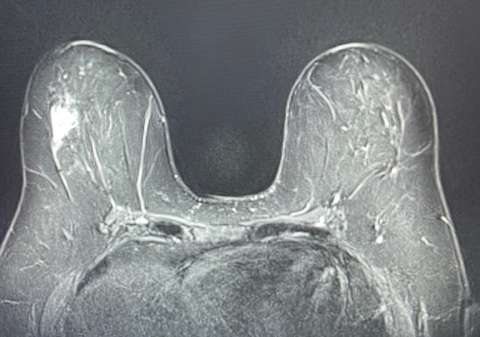

Breast Implant Associated Anaplastic Large Cell Lymphoma (BIA-ALCL) is a third type of lymphoma to be aware of in the breast. It is rare, affecting between 1 in 1000 and 1 in 10,000. As its name suggests, it is associated with breast implants and can present as a peri-implant fluid collection and/or a breast mass. Studies have shown that the majority of BIA-ALCL cases occur in people with textured implant envelopes, regardless of whether silicone or saline implants are used. Peri-implant fluid collections that appear more than 1 year after placement should be investigated. Typical onset of symptoms is 8-10 years after implant placement. After infectious causes are ruled out, the peri-implant fluid should be aspirated under ultrasound and sent for cytology.

MRI: Typically seen as round or oval mass, with T1 hypointensity or isointensity, and areas of T2 hyperintensity. Breast lymphomas may enhance homogenously or heterogeneously, with either slow or rapid enhancement, followed by a plateau in the delayed phase. MRI is very sensitive in evaluating the presence and extent of multicentric and multifocal lesions.